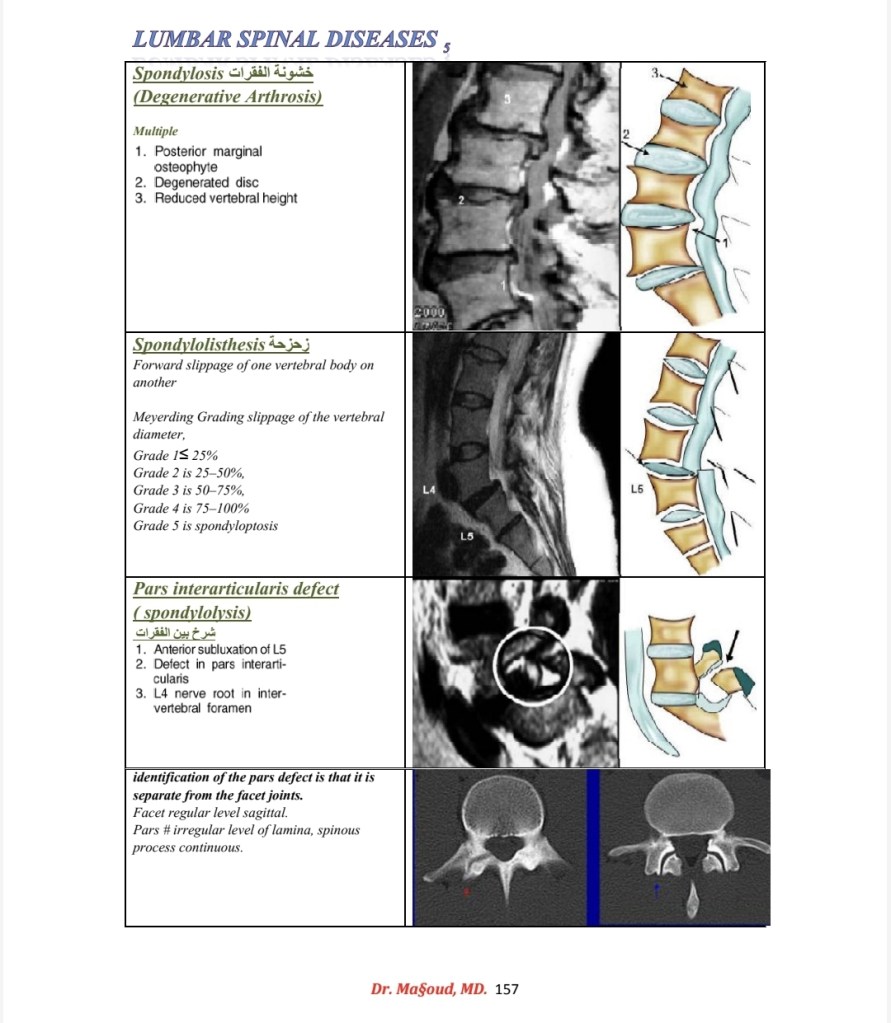

Spine imaging